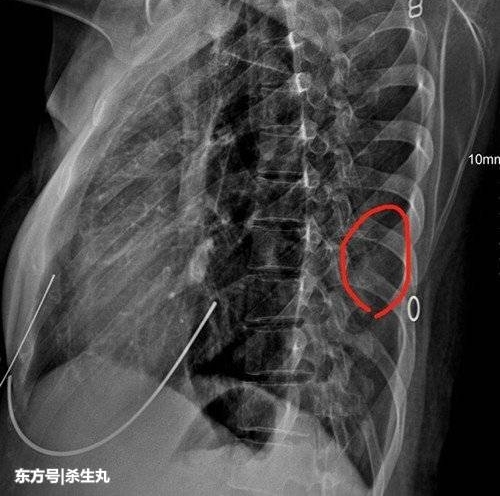

朋友赶过来时,小徐已经疼得无法动弹了。朋友把她送往本市一家医疗机构救治。医学影像图片显示,小徐的左十肋骨已经骨折。一声咳嗽,能把肋骨 " 咳断 "?对此,这家医疗机构的技术负责人葛延林说,在问诊时得知,小徐已经咳嗽一个月了。长期咳嗽导致肋部相关肌肉处于紧张状态,同时也会导致骨骼强度变弱。小徐在咳嗽时,肌肉会猛烈收缩,就把肋骨给 " 勒断 " 了。

医生处置好小徐的伤情后嘱咐她,咳嗽对肋骨骨折的愈合是潜在的不利因素,建议她积极治疗呼吸道原发病。同时,医生对她的肋部用护具固定,起到保护效果。